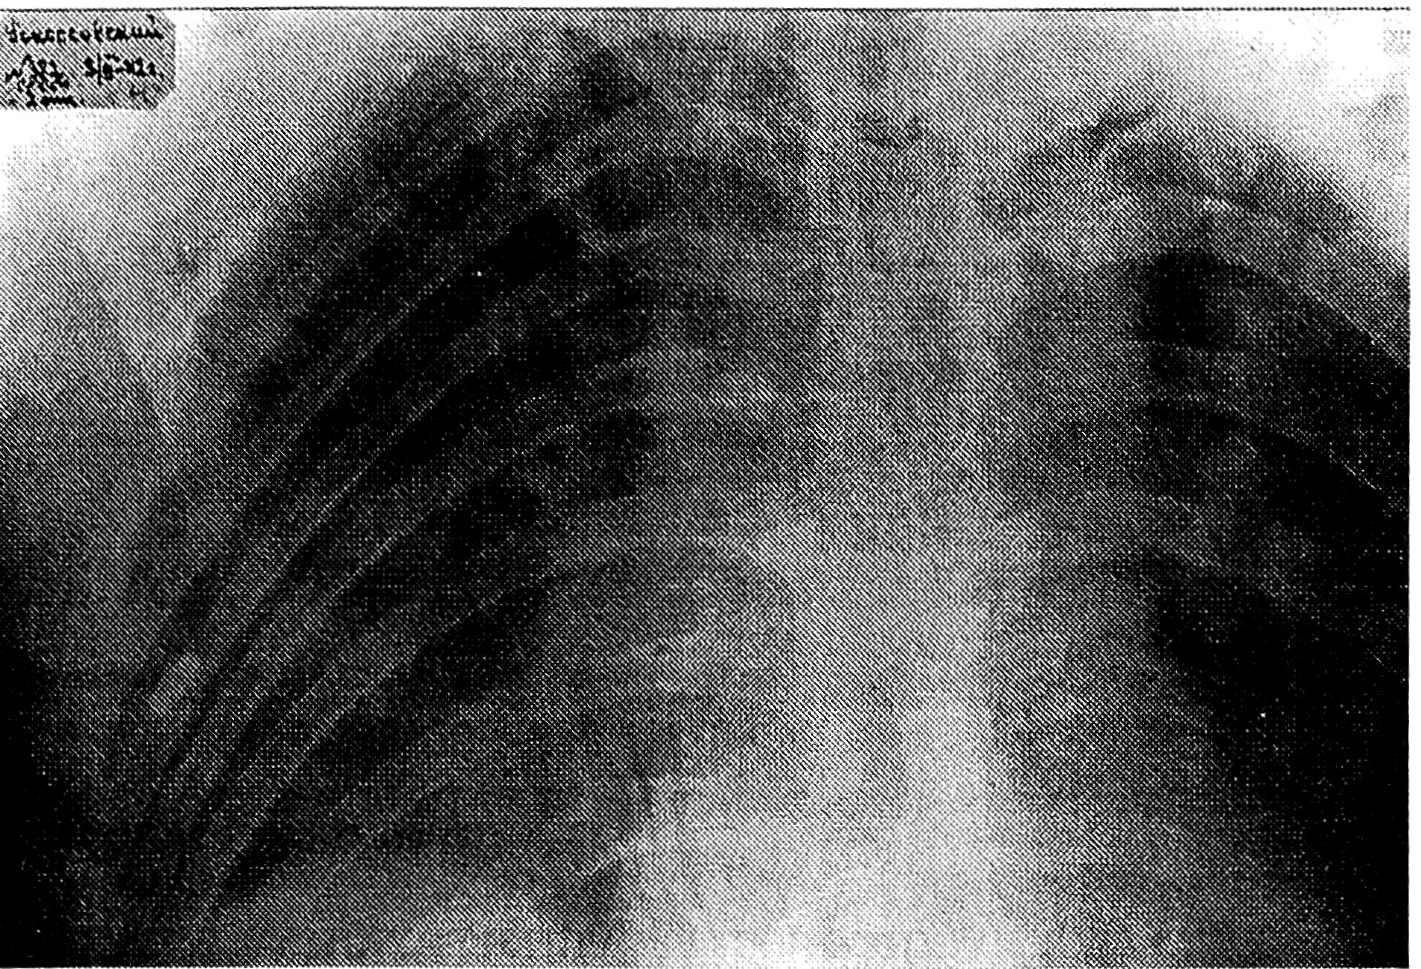

При рентгеноскопии грудной клетки определяется высокое стояние правого купола диафрагмы и ослабление его экскурсии по сравнению с левым куполом. Небольшое количество жидкости справа в нижней части плевральной полости. Легочные поля прозрачны. Большое количество газов в кишечнике. Обнаружен металлический осколок прямоугольной формы размером 1,2 × 0,4 см справа по задней аксиллярной линии на уровне VI ребра. Осколок расположен эксцентрично в легочной ткани. Имеется перелом правого XII ребра у основания с небольшим смещением. Сделана рентгенограмма.

Рис. 1. Рентгенограмма грудной клетки К.К. Рокоссовского от 9 марта 1942 г.

На основании обследования был ориентировочно определен ход раневого канала. Установлен диагноз: слепое проникающее сочетанное ранение печени, диафрагмы и правого легкого. Обнаруженный перелом XII ребра справа, видимо, произошел от ушиба при падении раненого. Состояние командарма очень тревожило. Назначив инъекции камфоры и морфия, я решил дать ему отдохнуть. Рокоссовский был помещен в генеральское отделение.